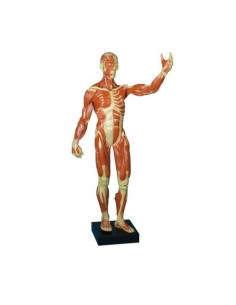

Scopri il Mondo dell’Anatomia con Modelli anatomici di Precisione

Benvenuto su Tuttoanatomia.it, il portale di riferimento in Italia per l’acquisto di modelli anatomici, poster, lettini portatili, simulatori medici e letteratura specialistica. Con i nostri modelli anatomici di 3B Scientific ed Erler Zimmer, leader mondiali nel settore, offriamo un’esperienza di apprendimento senza pari.

Modelli Anatomici Dettagliati per Ogni Necessità

Dal cranio in 22 parti con incastri magnetici ai modelli di colonna vertebrale, da quelli di articolazioni a quelli di cuore, ogni pezzo della nostra collezione è progettato per un’immersione totale nello studio dell’anatomia umana. I nostri modelli, realizzati tramite scansioni di ossa vere, garantiscono un’esperienza tattile autentica e una fedeltà di peso quasi identica agli originali.

Strumenti Didattici Innovativi per l’Educazione e la Pratica Medica

Essenziali per studenti e professionisti, i nostri modelli anatomici sono strumenti didattici che permettono di osservare le strutture anatomiche con precisione, eliminando la necessità di dissezioni o studi invasivi. Sono inoltre utili per spiegare ai pazienti le patologie, rendendo la comunicazione più efficace e risparmiando tempo prezioso.